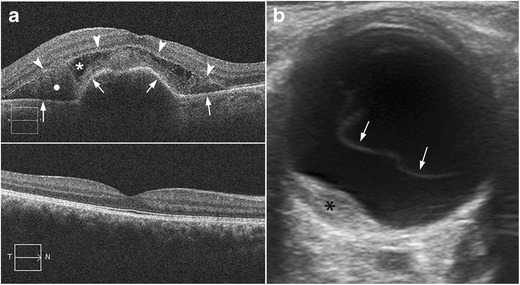

AMD is a chronic disease that causes vision loss in the centre of the field of vision. There are two major types of AMD: the atrophic or nonexudative type and the neovascular or exudative type. In neovascular AMD, the neovessels may bleed or leak, producing intra- and subretinal exudate and subsequently healing by fibrosis [1, 31]. The diagnosis is reached clinically with the aid of ophthalmologic tools such as fluorescein angiography and optical coherence tomography (Fig. 23). US may demonstrate an elevated mass on the posterior wall at the macular area that could be mistaken for a tumour (Fig. 23). These lesions are caused by subretinal exudates or haemorrhages in the region of the macula [1].

Fig. 23.

Neovascular age-related macular degeneration. a Top image: optical coherence tomography (OCT) image in a patient with active neovascular age-related macular degeneration (AMD) shows serous detachment of retinal pigment epithelium (arrows) and neurosensory retinal detachment (arrowheads). Note also the subretinal haemorrhage (white circle) and subretinal fluid (white asterisk). Bottom image: non-pathologic OCT in another patient. b 71-year-old man with progressive vision loss in the right eye. US shows a mass on the temporal side of the posterior wall next to the papilla (asterisk); note also the posterior vitreous detachment (arrows). Final diagnosis was subretinal haemorrhage due to choroidal neovessels in the context of neovascular AMD